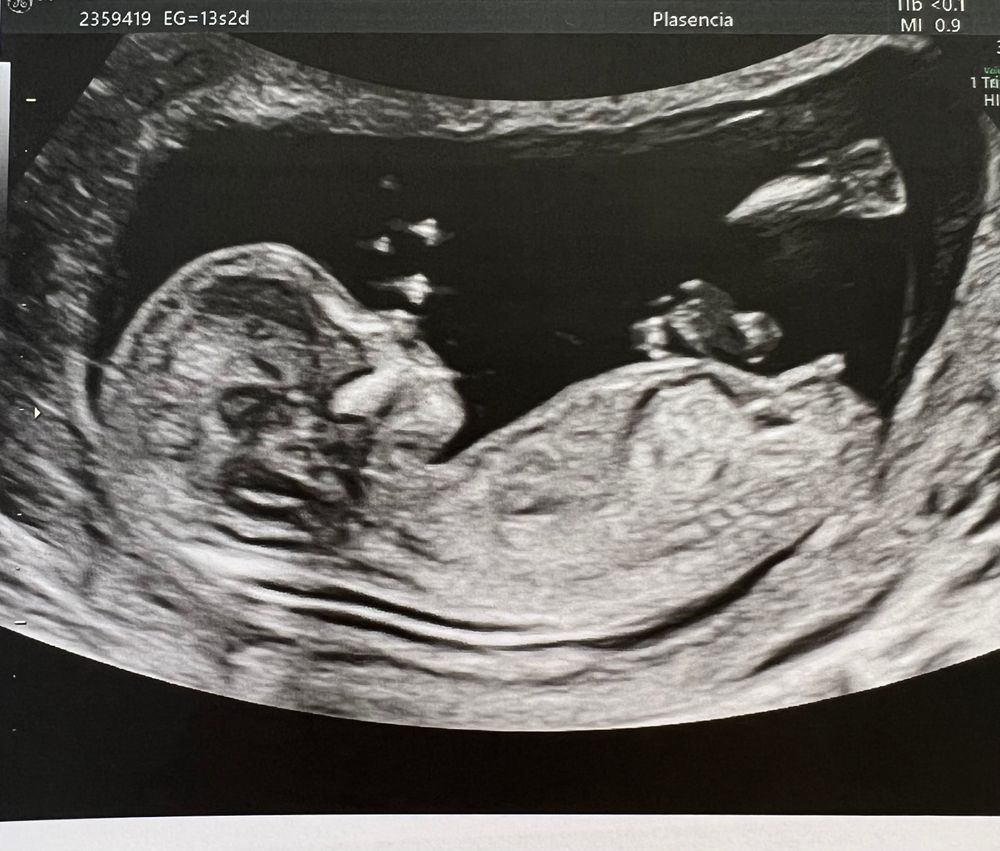

Первый скрининг! Девочка? 😃🎀

Поздравляю вас, а у вас какая неделя?)

Счастливая по жизни , спасибо 😇 идёт 14-ая

Высокое ЧСС? Короткая шейка. Ктг. Попыталась понять сама. Не получилось